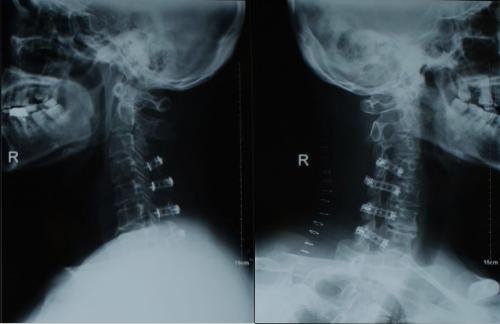

6.手术治疗

严重有神经根或脊髓压迫者,必要时可手术治疗。